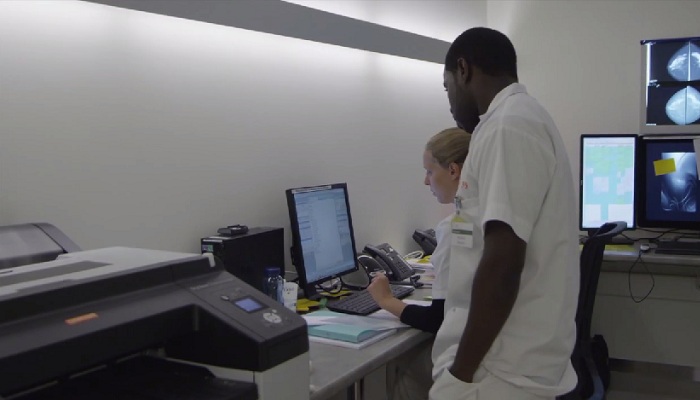

« Le mammographe numérique plein champ Philips MicroDose est un dispositif médical de classe IIb, fabriqué par Philips Healthcare, dont l’évaluation de la conformité a été réalisée par l’organisme certifié DET NORSKE VERITAS 0434. La technologie brevetée du compteur de photons utilisée par le système constitue une aide à la détection du cancer du sein, avec une faible dose d’irradiation. Les actes effectués avec le système MicroDose de Philips sont pris en charge par les organismes d’assurance maladie dans certaines situations. Lisez attentivement le manuel d’utilisation. Ce dispositif médical est un produit de santé réglementé qui porte, au titre de cette réglementation, le marquage CE. »